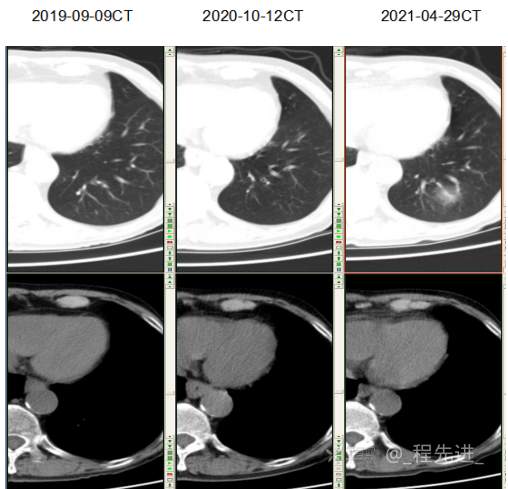

主诉: 反复咳嗽、咳痰10余年,加重10余天

现病史:患者10年前开始出现反复咳嗽、咳痰,3年前出现活动性气喘,休息后症状可缓解;冬春季节或受凉后症状加重,不伴反复下肢浮肿,曾在我院住院诊断为”慢性阻塞性肺疾病”,给予解痉平喘、化痰、输氧治疗有效,平素生活能自理,不能从事体力劳作,此次发病于10天前可能受凉后咳嗽、咳痰加重,咳黄痰,呈阵咳,咳白痰,活动气喘加重,不伴畏寒、发热,无胸痛,今来我院就诊,拟“慢性阻塞性肺病伴急性加重”收住入院,自发病以来,患者精神、食纳、睡眠一般,大小便如常,体重有下降,县体不详。患者及陪护人员:否认14天内离开过南丰,否认14天内有新型冠状病毒感染病例报告社区或中高风险地区的旅行史或居住史,否认14天内与新型冠状病毒感染的患者或无症状感染者有接触史,否认14天内曾接触过来自有病例报告社区或中高风险地区的发热或有呼吸道症状的患者,否认14天内在小范围如家庭、办公室、学校班级等场所,出现5例及以上发热和/或呼吸道症状的聚集性发病病例。